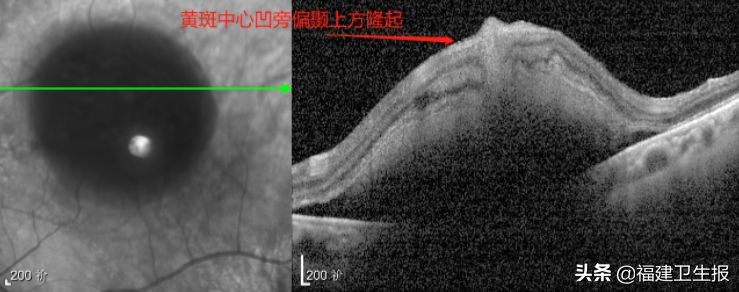

专科检查:左眼视力裸眼:0.1- 矫正无提高,眼压16.3mmHg,黄斑中心凹见一大小约10PD暗红色出血灶,眼底照相、OCT、FFA和ICGA的检查如下:

▲入院当天OCT检查

同时,他们发现:孙阿婆左眼白内障可以手术,黄斑中心凹旁偏颞上方隆起约1435um(约1.5mm),黄斑区出血面积约10PD,出血时间在1周左右,符合视网膜下tPA注射术手术指征。